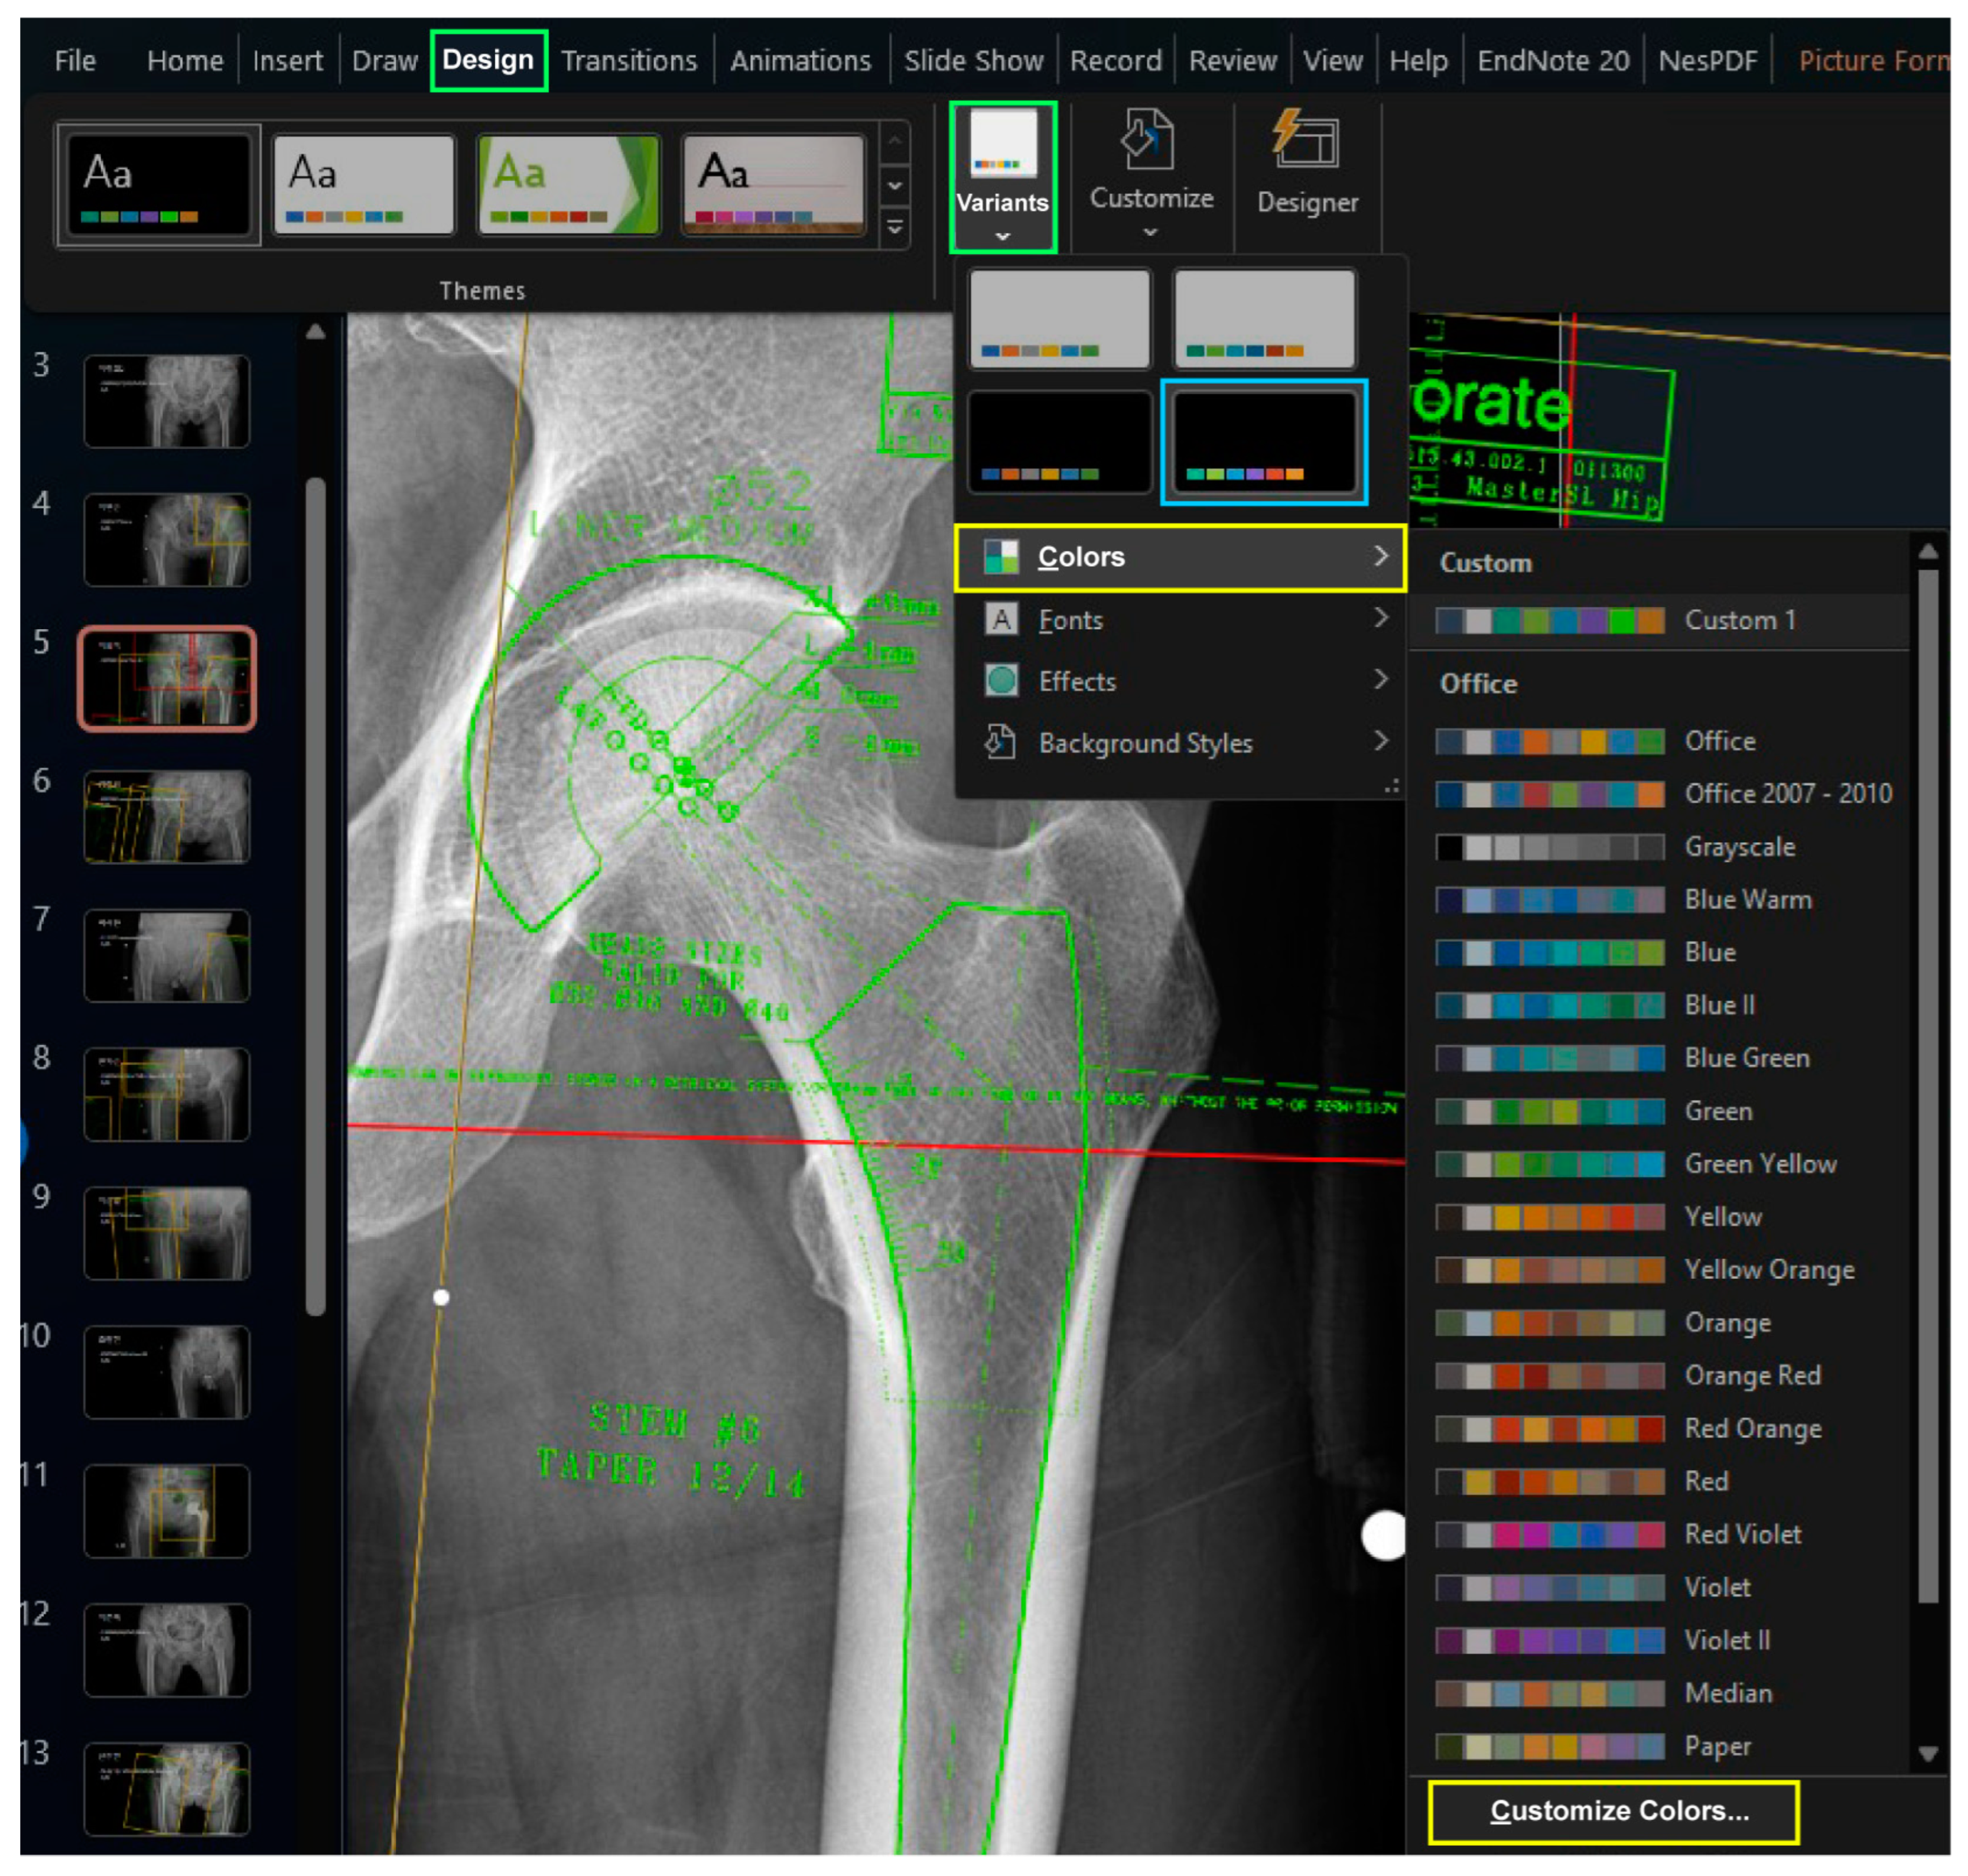

When creating these two files, it is recommended to maintain an identical design theme to ensure consistent colors when copying an image from the “Armamentarium” PowerPoint file to the “Templating” PowerPoint file. It is recommended to select a variant with black background color from the default design themes in the “Design” Table Additionally, customizing the six accent colors is advised, as they will be used for the template images. To define the accent colors, select the “Customize Colors” command by clicking on the downward arrow under the “Colors” button after selecting the downward tab of “Variants” in the “Design” tab (Figure 1).

Figure 1. The design theme affects the background color and accent colors. Among the variants of the default theme (green boxes), a theme with a black background can be found (blue box). In the dropdown menu of variants (green box), one can customize the accent colors (yellow boxes).